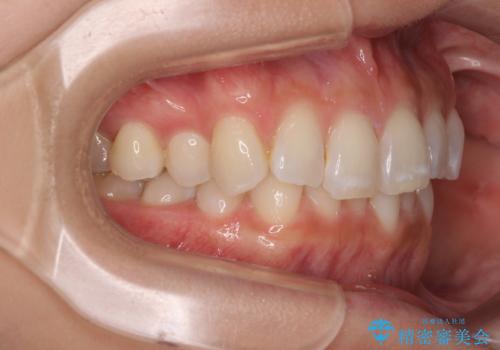

- 上下前歯のデコボコとディープバイトを気にして来院された患者様です。

歯列全体に叢生があり、舌の突出癖が認められたため、突出癖が改善されない場合には口元が突出するリスクが考えられました。

マウスピースでもワイヤーでも対応可能でしたが、煩わしいことは避けたいとのことで、舌のトレーニングをしっかりと行っていただきながら、ワイヤー装置にて矯正治療を行うこととしました。